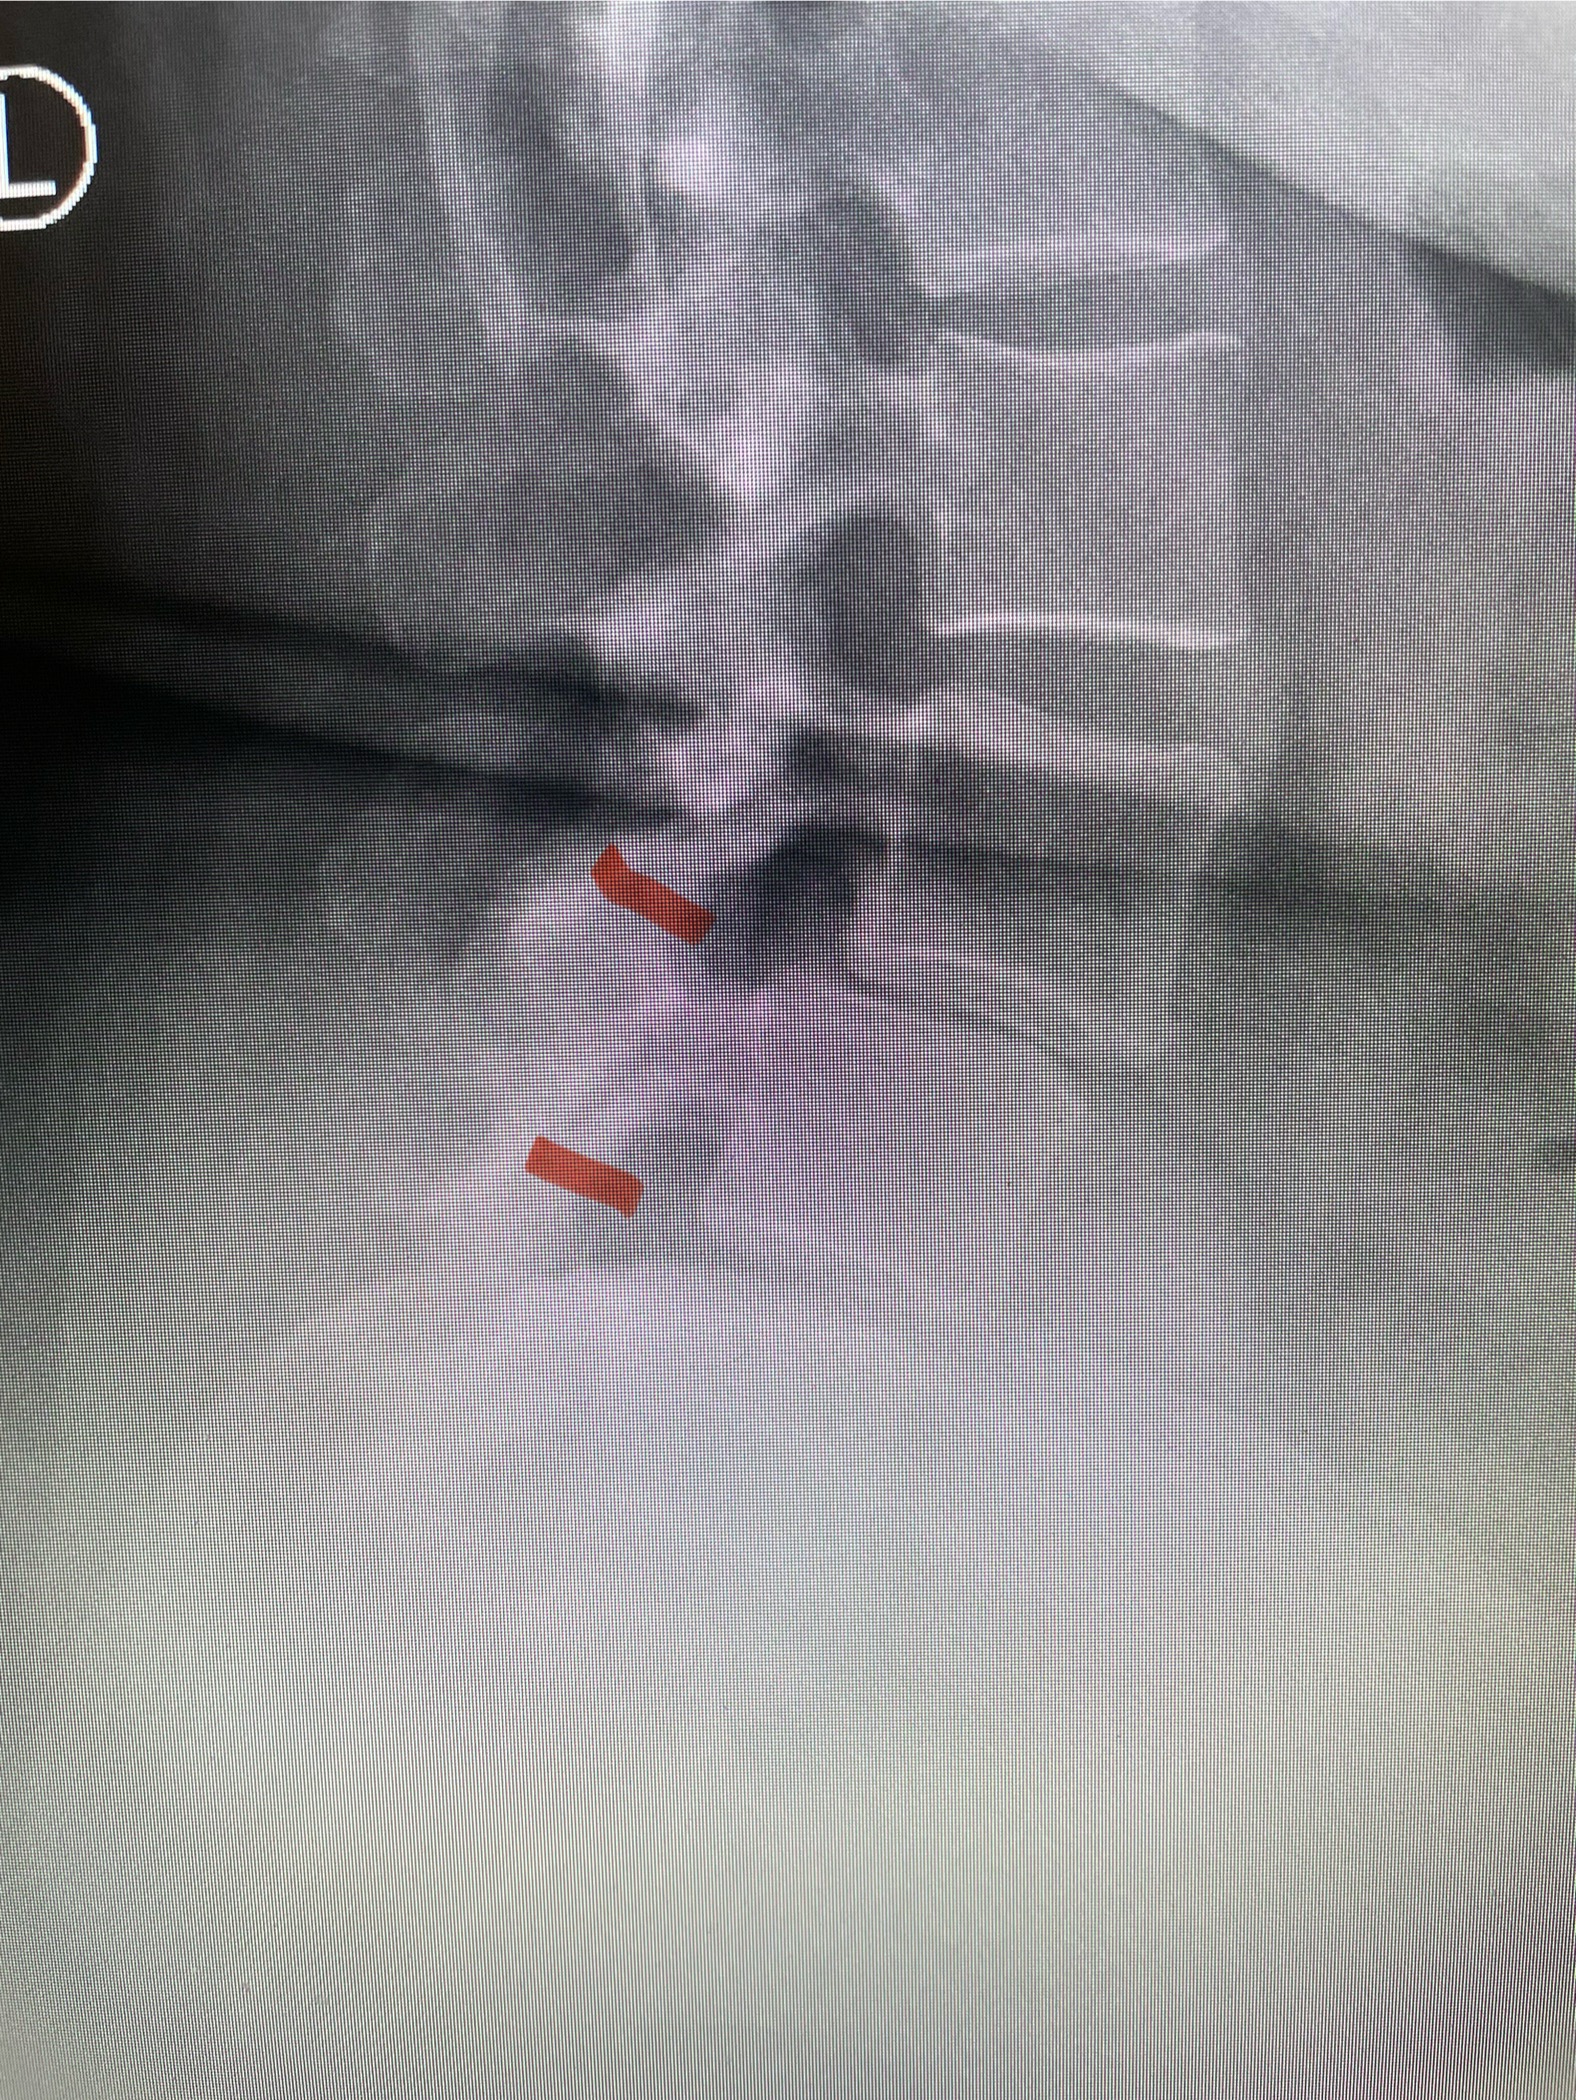

The patient had failed all means of conservative management including Physical Therapy and epidurals. He had an extensive medical history including stroke, cardiac stents, diabetes on insulin, hypertension, hypercholesterolemia, and kidney disease. Since he had a prior fusion with instrumentation for L4-S1, it was interesting that the patient had not developed significant next segment stenosis at L3-4. However, CT analysis (Fig. 2) demonstrated a partial fusion that extended from L3 to L4 which prevented abnormal motion.

Fig 2: Coronal lumbar CT demonstrating L4-S1 fusion with instrumentation with some incomplete bony fusion to the L3-4 segment (red arrow)